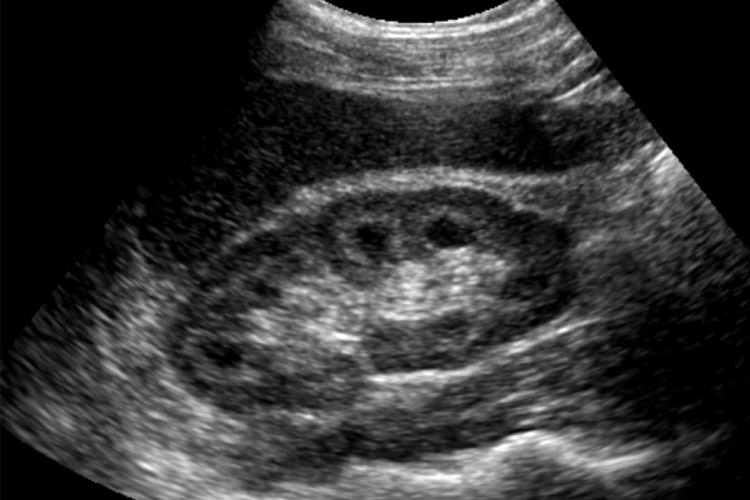

Η εξέταση των νεφρών συμβάλει στον προσδιορισμό της θέσης, του μεγέθους καθώς και του σχήματός τους. Ελέγχεται η παρουσία ή όχι λίθου, τυχόν διάταση του πυελοκαλυκικού συστήματος (αποφρακτικά φαινόμενα) καθώς και άλλες διαταραχές της ηχομορφολογίας (π.χ. ανατομικές παραλλαγές, αλλοιώσεις σε έδαφος νεφρικής ανεπάρκειας). Σημαντικός ο ρόλος στην απεικόνιση εστιακών αλλοιώσεων τόσο με καλοήθεις όσο και με κακοήθεις χαρακτήρες.